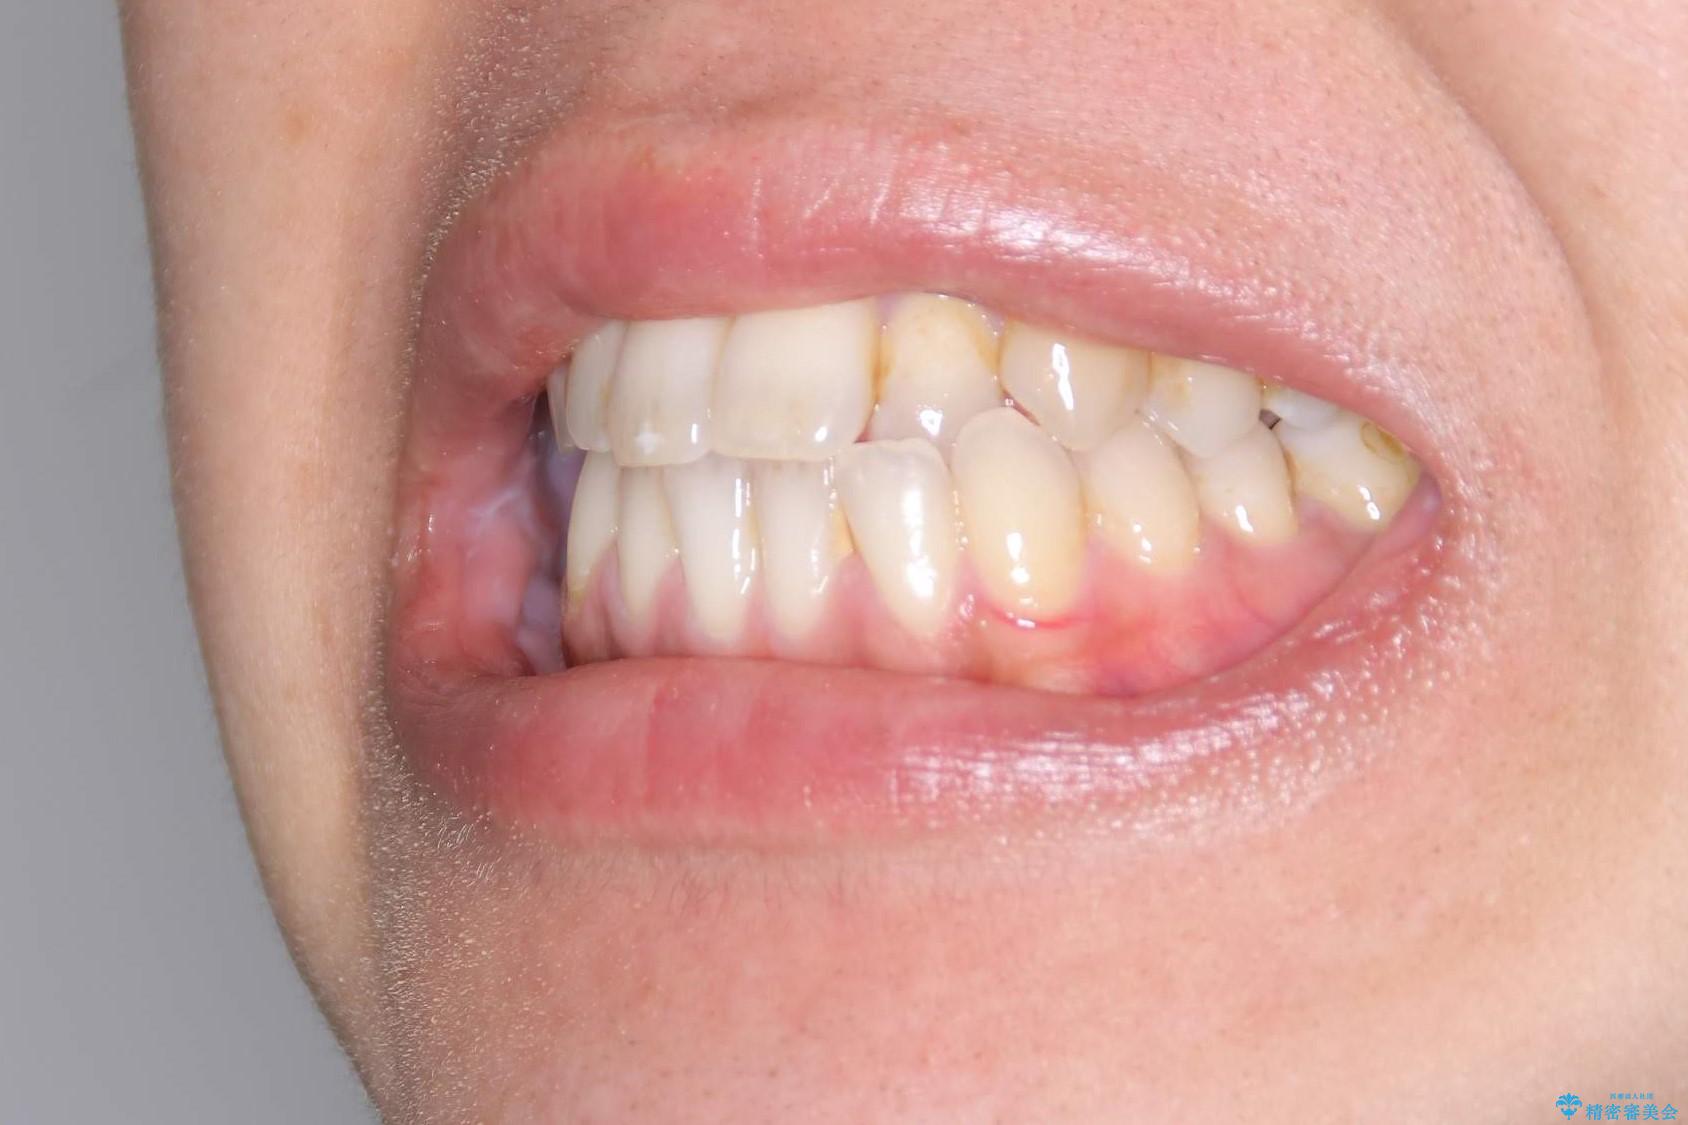

Invisalign インビザライン によるガタつき、受け口傾向の改善

奥歯の位置関係の修正は難儀することが多いマウスピース矯正ですが、割とスムーズに奥歯の位置関係の修正をすることができました。

クロスバイトもきれいになり、きれいな歯並びとなりました。